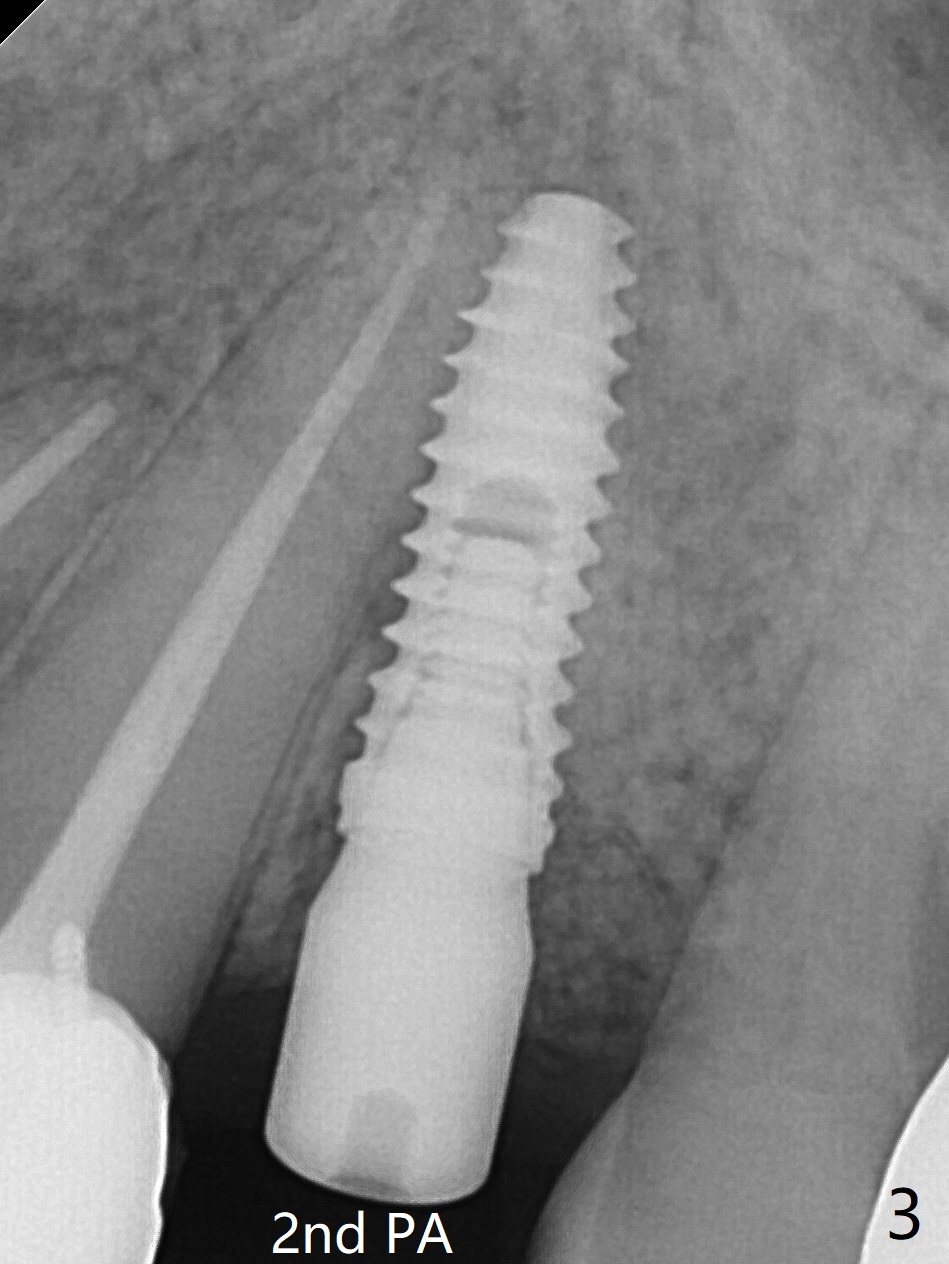

植骨后6个月牙槽窝愈合正常,角化龈和牙槽嵴都宽(图一),导板种植好像不需要切口。利用导板植入,但是离尖牙牙根很近(图二,三)。取出植体后,准备切开改变钻洞方向(图四,五),结果效果不错(图六,七),腭侧骨壁低,安置愈合基台,植骨(图八:*),覆盖胎盘膜,缝合。